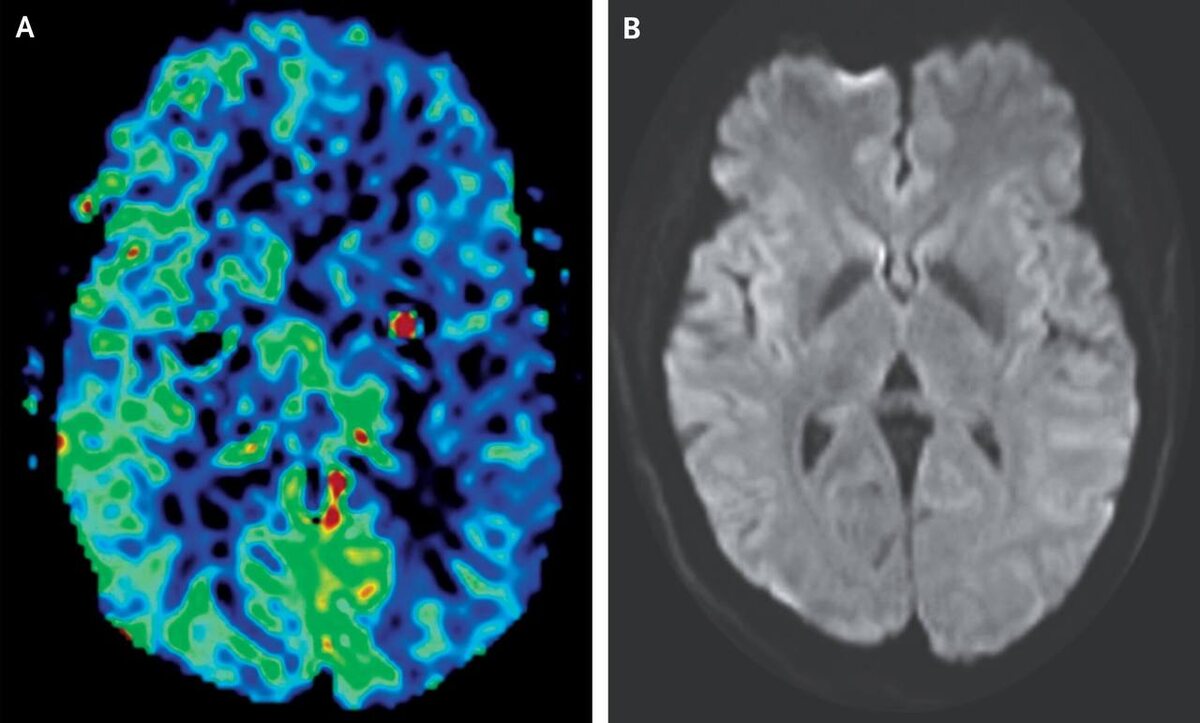

46-летняя женщина обратилась в больницу с симптомами, напоминающими инсульт: пульсирующая головная боль, слабость и онемение правой руки.

Однако МРТ и ангиография не выявили признаков инсульта. Вместо этого был поставлен диагноз гемиплегической мигрени — редкой формы мигрени с аурой, при которой наблюдается временная слабость или паралич с одной стороны тела. Эта форма мигрени сопровождается гипоперфузией мозга, что объясняет симптомы.

Женщина получила лечение, и её состояние улучшилось: головная боль прошла через 45 минут, а слабость — через полтора часа. Она была выписана с рекомендациями для амбулаторного наблюдения.